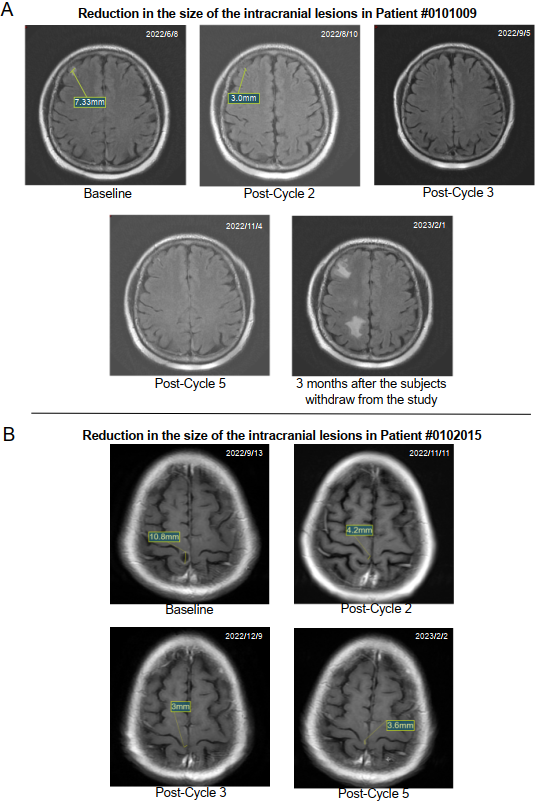

圖2展示了兩例典型患者的腦部MRI影像。這些患者的中位緩解時(shí)間為1.8個(gè)月(范圍:1.7-1.8),中位顱內(nèi)PFS(IC-PFS)為8.0個(gè)月(95%CI:4.7-16.0)。顱內(nèi)療效采用改良實(shí)體瘤療效評(píng)價(jià)標(biāo)準(zhǔn)(RECIST 1.1)評(píng)估。

圖1展示了17例腦轉(zhuǎn)移患者的緩解深度。顱內(nèi)ORR(IC-ORR)為41%(7/17;95%CI:18.4%-67.1%),顱內(nèi)DCR(IC-DCR)為76%(13/17;95%CI:50.1%-93.2%),中位顱內(nèi)緩解深度(IC-DepOR)為34.4%(范圍:0.4%-100%)。

在腦轉(zhuǎn)移亞組中,17例完成至少一次治療后評(píng)估的患者納入療效分析。中位隨訪時(shí)間23.9個(gè)月。ORR為53%(9/17;95%CI:27.8%-77.0%),總體DCR為71%(12/17;95%CI:44.0%-89.7%),中位緩解深度(DepOR)為45.5%(范圍:5.0%-85.5%)。中位全身PFS為5.7個(gè)月,中位顱內(nèi)PFS為9.8個(gè)月(對(duì)于因全身療效評(píng)估為PD而終止治療但腦病灶未達(dá)PD標(biāo)準(zhǔn)的患者,其顱內(nèi)PFS以終止治療日期作為截尾值)??偵嫫冢?/span>OS)數(shù)據(jù)尚未成熟。11例活動(dòng)性腦轉(zhuǎn)移患者的顱內(nèi)ORR(iORR)為54.5%(6/11),顱內(nèi)DCR(iDCR)為72.7%(8/11);3例穩(wěn)定/已治療腦轉(zhuǎn)移患者的iORR為33.3%(1/3),iDCR為100%(3/3);3例軟腦膜轉(zhuǎn)移患者的iORR為0%(0/3),iDCR為66.7%(2/3)。